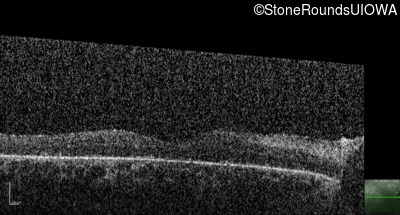

Optical Coherence Tomography - Left - Hand Motion

Exemplar / OCT Stack